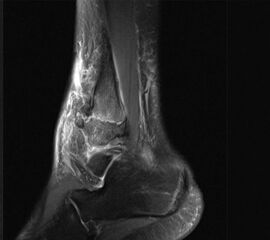

MRT

Die Kernspintomographie hat ihre Stärke in der Darstellung von Weichteilverletzungen. Insbesondere Verletzungen der Wachstumsfuge, des Periosts und der Bänder lassen sich gut visualisieren. Nachteilig ist die Untersuchungsdauer von 20-30 Minuten. Bleibt das Kind während dieser Zeit nicht ruhig liegen, kommt es zu Bewegungsartefakten, welche die Beurteilbarkeit der Bilder beeinträchtigen.

Fugengelenkfrakturen treten typischerweise vor dem 10. Lebensjahr auf, in einer Phase, in welcher die Wachstumsfugen noch weit offen sind. Dieser Frakturtyp betrifft fast ausschließlich den medialen Malleolus. Laterale Frakturen sind extrem selten, teilweise kommt es zu lateralen Bandverletzungen oder Fugenschaftfrakturen der distalen Fibula. Die Frakturlinie verläuft in einer Verlängerungslinie von der medialen Taluskante nach proximal. Häufig stellen sich Verletzungen des Innenknöchels im Röntgenbild schlechter dar, insbesondere wenn die Aufnahmen verdreht sind oder die Ebene der Fraktur bei geringer Dislokation verkippt zur Röntgenebene liegt. Besteht klinisch der geringste Hinweis auf eine Verletzung des Innenknöchels, muss aufgrund der Tragweite der Verletzung durch entsprechende Aufnahmen gegebenenfalls auch Schnittbildverfahren die Verletzung sicher diagnostiziert oder ausgeschlossen werden (Abb. 15).